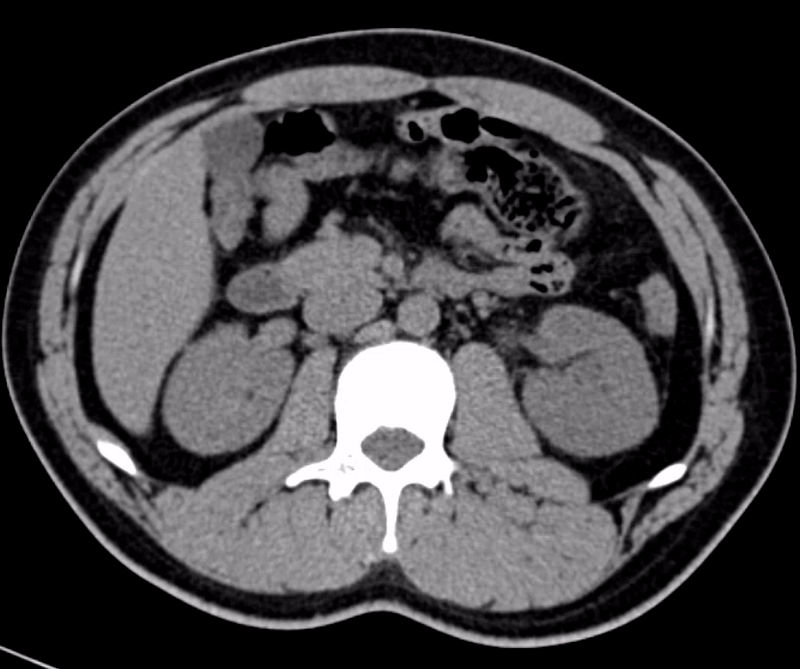

影像科康龙山和张光源借着丰富的经验和敏锐的观察力,发现了罗先生左侧输尿管上段有结石。泌尿外科根据影像结果,立即制定出了针对性的治疗方案。经过精心治疗,罗先生体内的结石成功被清除,身体逐渐恢复了健康。罗先生康复后满怀感激之情,特意手写感谢信,以表达对影像科的感谢。